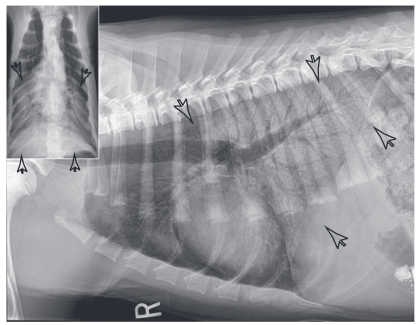

What distribution does this lung pattern have and therefore what is the most likely cause?

Bilateral caudodorsal alveolar pattern, more likely pulmonary oedema